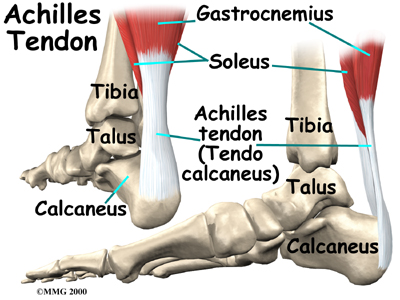

The ankle joint is also supported by nearby tendons. The large is the most important tendon for walking, running, and jumping. It attaches the calf muscles to the calcaneus (heelbone) and allows us to raise up on our toes. The attatches one of the smaller muscles of the calf to the underside of the foot. This tendon helps support the arch and allows us to turn the foot inward.

- The calf muscles (gastrocnemius and soleus) connect to the calcaneus by the Achilles tendon. When the calf muscles tighten, they bend the ankle down.